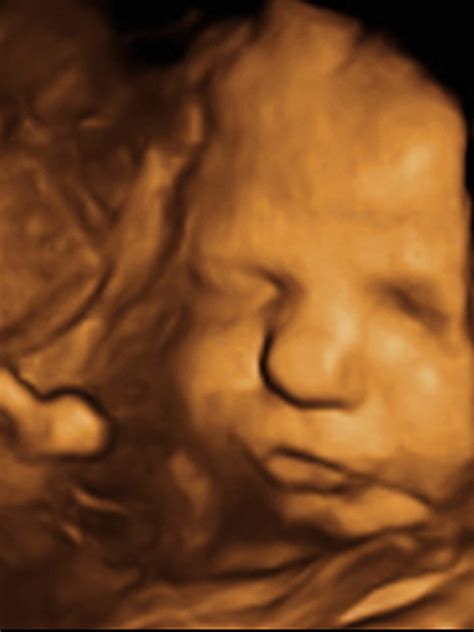

3D ultrazvuk predstavuje statické zobrazenie plodu v priestore, v trojrozmernom obraze. Vzniká počítačovým spracovaním súboru nakumulovaných 2D obrazov. Umožňuje vidieť dieťatko v plastickom zobrazení, čo je pre rodičov často emocionálne veľmi silný zážitok. Umožňuje vidieť črty tváre a dokonca aj podobu dieťatka.

4D ultrazvuk nadstavuje 3D zobrazenie o rozmer času, teda pohybu. V 4D zobrazení vidíte dieťa v priamom prenose, môžete sledovať jeho pohyby, mimiku a interakcie v reálnom čase. Toto vyšetrenie je obľúbené pre svoju schopnosť zachytiť živé momenty zvnútra maternice.